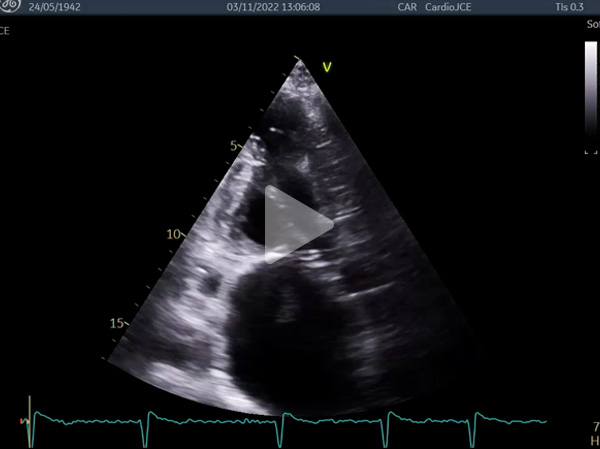

Vidéo 1 : HVG concentrique, petite cavité VG, dilatation biatriale sévère

Vidéo 2 : anévrysme apical

- Échocardiogramme transthoracique : volumineux thrombus de 40 mm de diamètre au toit de l’OG

Vidéos 5 à 7 et figure 9 : Masse arrondie de 43 mm de diamètre flottant librement dans l’oreillette gauche avec enclavement périodique dans l’orifice mitral : « ball thrombus »